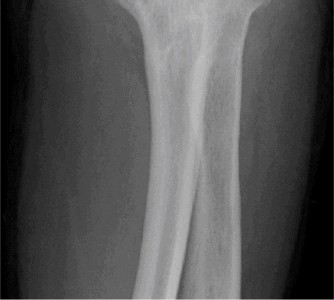

The correct answer is (E). Given that her rotator cuff has atrophied and has fatty infiltration to the point where there are equal parts fat and muscle, this is considered an irreparable rotator cuff tear. Repair should not be attempted because of poor outcomes following repair (see last two paragraphs of this discussion below). A reverse total shoulder arthroplasty is an alternative to repair that should be used in cases of massive, irreparable rotator cuff tears. It is a semi-constrained prosthesis that restores function in patients with massive rotator cuff tears by constraining a concave humeral cap inferior to a semispherical glenoid component (glenosphere). This creates an inferior force-couple and a fulcrum that replaces the stabilizing function of the infraspinatus maintaining a center of rotation around which the shoulder can move. This allows the deltoid to abduct and flex the shoulder without causing the humerus to migrate superiorly and about the acromion. In an elderly patient with a massive, irreparable rotator cuff tear (as in this patient), a reverse total shoulder arthroplasty is the procedure of choice.

It should be noted that reverse total shoulder arthroplasty is also the procedure of choice in patients with cuff-tear arthropathy (aka rotator cuff arthropathy). Characteristics of cuff-tear arthropathy include superior migration of the humerus due to a massive rotator cuff tear, glenohumeral joint destruction, subchondral osteoporosis, and humeral head collapse (see Fig. 2–17). A reverse total shoulder

Figure 2–17_X-rays of a patient showing evidence of cuff tear arthropathy. The humerus is migrated superiorly, the glenohumeral joint is destroyed, there is subchondral osteoporosis, and the humeral head is collapsed. (From Ecklund KJ, Lee TQ, Tibone J, Gupta R. Rotator cuff tear arthropathy. _J Am Acad Orthop Surg. 2007;15(6):340–349.)